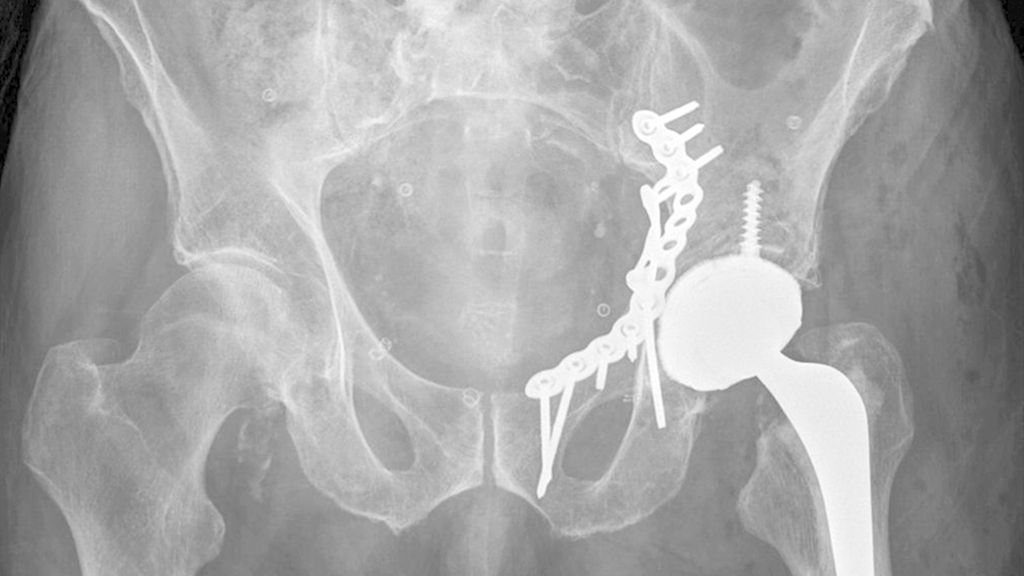

Die Mehrheit der Herausforderungen bei der Behandlung der Fragilitätsfraktur des Acetabulums überschneidet sich mit denen bei Beckenringfraktur. Ebenso wenig überraschend treten auch auf der anderen Seite des Hüftgelenkes ähnliche Komplikationen und eine Reduktion der Lebenserwartung wie bei hüftnahen Oberschenkelfrakturen auf. Im Unterschied zu den FFP gilt dieselbe Klassifikation für Hochrasanz- und Niedrigenergietraumata des Acetabulums nach Judet und Letournel. Der große Unterschied besteht jedoch in der Häufigkeitsverteilung. Aufgrund der meist einfachen Stürze mit Gewalteinwirkung über den Trochanter major betreffen die Fragilitätsfrakturen des Acetabulums meist den vorderen Pfeiler und die quadrilaterale Fläche. Entsprechend sind dislozierte Frakturen eine Domäne der offenen Operationsverfahren und der Hüftendoprothetik. Der Stellenwert der minimalinvasiven Stabilisierung nicht dislozierter Acetabulumfrakturen und der Stabilisierungen in Fehlstellung ist wissenschaftlich nicht geklärt. Jedoch gibt es zunehmende Literatur über das sogenannte „fix and replace“, bei dem eine Osteosynthese eines Pfeilers mit einer primären Totalendoprothese in einer Operation kombiniert wird (Abb. 2).

Abb. 2: „Fix and replace“ mit Osteosynthese und Hüfttotalendoprothese in der selben Operation bei geriatrischer Acetabulumfraktur mit Impressionsfraktur des Doms

Bisher konnten dabei keine erhöhten Komplikationsraten gegenüber der konventionellen Osteosynthese festgestellt werden. Gleichzeitig besteht aber der Vorteil der Vollbelastbarkeit, des Einsatzes einer konventionellen Pfanne und der in der Orthogeriatrie erwünschten „one-shot surgery“ (nur eine Operation statt einer potenziellen zweiten Operation bei Versagen der Osteosynthese und sekundärer Prothese). Bei ca. 30% der geriatrischen Acetabulum-Osteosynthesen in der Literatur erfolgte eine Revision mittels Prothese. Risikofaktoren für die Notwendigkeit einer sekundären Hüfttotalendoprothese nach Osteosynthese sind: höheres Alter, Impressionsfrakturen des Doms und Hüftkopfes, Medialisierung des Hüftkopfes („zentrale Hüftluxation“), nichtanatomische Reposition (häufig durch späte Versorgung nach konservativem Therapieversuch oder längerer Operationsvorbereitung bei Multimorbidität).

Im Gegenzug dazu wird in der Literatur auch eine minimalinvasive offene Osteosynthese beschrieben, wobei man auf ausgedehnte Repositionsmanöver mit dem damit verbundenen Blutverlust verzichtet. Dadurch werden zum Teil verbliebene Fehlstellungen akzeptiert bzw. wird durch postoperative Mobilisierung eine sekundäre Dislokation in Kauf genommen, um eine postoperative Vollbelastung zu ermöglichen. Eine entsprechende Operationstechnik über einen Stoppa-Zugang und mit Plattendesign mit Abstützung der quadrilateralen Fläche wurde durch Culemann 2023 anschaulich beschrieben.12 Bei geschwächter Knochenqualität ist neben dem Plattendesign mit medialer Abstützung an der quadrilateralen Fläche auch das Augenmerk auf eine stabile Verankerung zu legen. Die infraacetabuläre hintere Pfeiler-Schraube, welche meist um die 100mm Länge aufweist, ist hierbei sehr empfehlenswert (Abb. 2 und Culemann 202312).